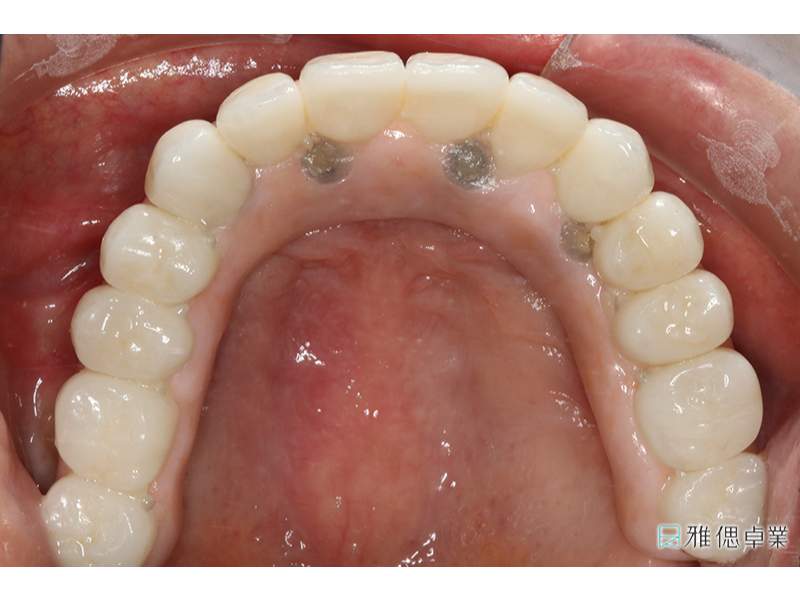

All on 6正式假牙(上顎)

口內取定位模型

全口假牙模型,模擬自然牙支台齒

假牙模型上顎